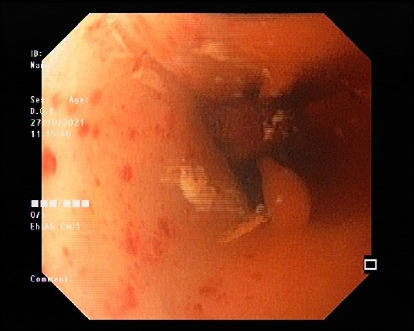

背景:食管胚胎性横纹肌肉瘤(ERMS)是一种罕见的儿童癌症,在一个涉及吞咽困难和呕吐的病例中模仿贲门失弛缓症。由于潜在的并发症,诊断和化疗需要仔细监测。病例介绍:一名12岁女孩,无既往病史,表现为进行性吞咽困难和呕吐。初步诊断为贲门失弛缓症,但进一步检查发现一个大的纵隔肿块引起食管压迫。活检证实原发性食管ERMS伴转移。尽管化疗,她出现并发症,包括中性粒细胞减少性小肠结肠炎和后部可逆性脑病综合征(PRES)。不幸的是,她死于中性粒细胞减少性败血症。结论:在本病例研究中,除了文献中有限的信息外,我们还介绍了我们对该疾病的临床病程、治疗策略和预后的经验。

Background: Esophageal embryonal rhabdomyosarcoma (ERMS), a rare pediatric cancer, mimicked achalasia in a case involving dysphagia and vomiting. Diagnosis and chemotherapy necessitate careful monitoring due to potential complications. Case presentation: A 12-year-old girl with no prior medical history presented with progressive dysphagia and vomiting. Initial diagnosis suggested achalasia, but further evaluation revealed a large mediastinal mass causing esophageal compression. Biopsies confirmed primary ERMS of the esophagus with metastases. Despite chemotherapy, she developed complications, including neutropenic enterocolitis and posterior reversible encephalopathy syndrome (PRES). Unfortunately, she succumbed to neutropenic sepsis. Conclusion: In this case study, we presented our experience regarding the clinical course of this disease, treatment strategy, and prognosis, in addition to the limited previous information in the literature.